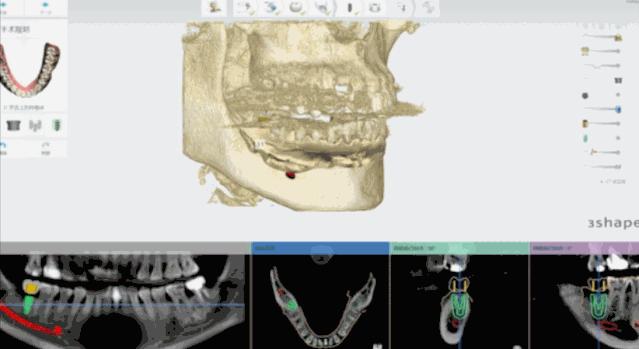

日照口腔医院种植中心配置先进的种植手术室,为患者提供各种类型的种植义齿修复,在日照市最早开展口腔种植技术,采用先进的医疗技术装备和世界一流的种植系统,配备有丹麦3shape口内扫描仪、Yoshida激光治疗仪、卡瓦(KaVo)锥形束CT、超声骨刀等国际先进仪器和设备,装备有瑞士士卓曼等多套国际种植系统,同时配备国际一流的消毒供应室,为疑难复杂病例的诊治提供了必要条件。

医院开展CAD/CAM数字化种植导板技术,通过整合数字化影像、cbct 数据以及数字化加工技术的新型种植导板,充分考虑到了颌骨条件、口腔解剖结构以及修复效果的结合,且精确度高,手术安全性高